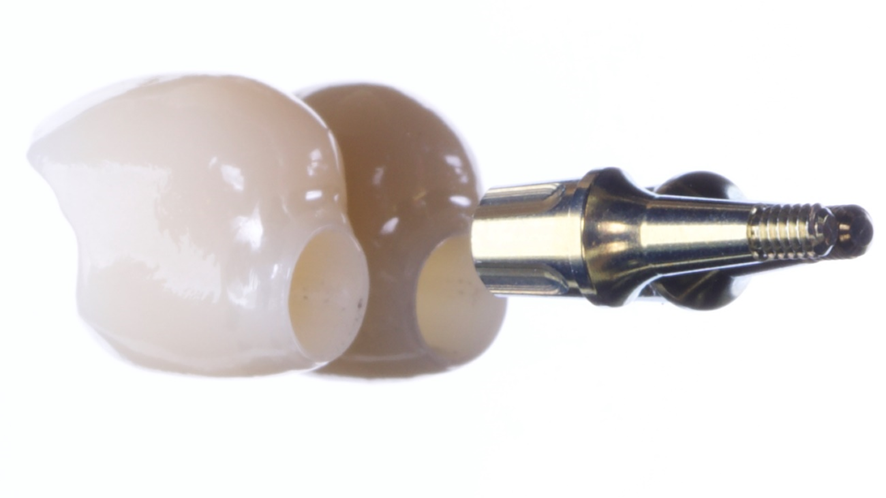

Existem alguns fatores que influenciam na seleção dos materiais provisórios, tais como: potencial estético, o tempo de tratamento, facilidade na remoção e durabilidade. Com o uso do planejamento digital, conseguimos buscar uma estética imediata provisória mais previsível e com materiais mais refinados como os provisórios em PMMA (Polimetilmetacrilato), no qual é possível personalizar o tamanho, cor, perfil de emergência do dente, otimizando o resultado para a futura prótese definitiva.5

O PMMA é um material biocompatível com os tecidos periapicais, radiotransparente e rígido, de modo que apresenta bons resultados estéticos, sendo planejado antes da cirurgia e podendo ser instalado do pós-operatório mediado ou imediato.3

Em seguida foi realizado a captura do provisório em PMMA na coifa de titânio com resina fluida e após acréscimos, acabamento e polimento fora da boca, o provisório foi aparafusado e a cirurgia foi finalizada sem a necessidade de sutura.

Após o período de seis meses de acanhamento clínico foi realizado a confecção da coroa definitiva. Tendo como passo inicial a remoção da coroa provisória feita de PMMA, sobre o qual foi observado um excelente perfil de emergência, e realizado o escaneamento da região com o transfer digital do pilar Ideale de 4,5x4mm, e escaneamento do provisório, o laboratório confeccionou uma coroa definitiva de zircônia monolítica baseada no perfil de emergência do provisório escaneado e o conjunto foi levado a boca e aparafusado com parafuso Torx (Implacil De Bortoli).